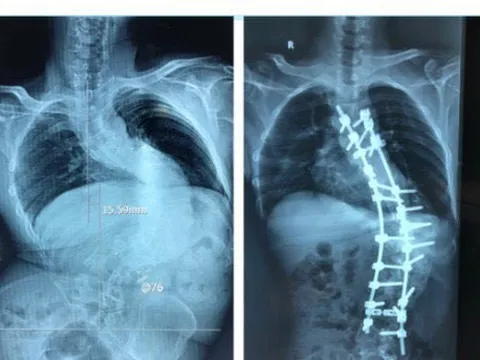

Tìm lại vóc dáng cho bệnh nhân bị biến dạng cột sống kèm gù hơn 100 độ